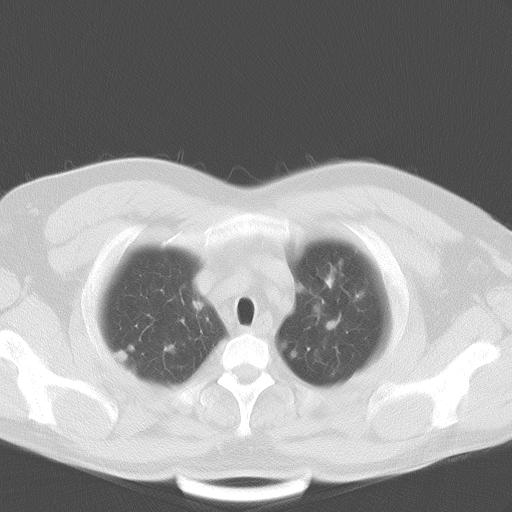

患者男性 35 主因发热咳嗽四天,血象不高,心肺听诊未见异常,无其它病史及传染病接触史。

两肺散在大小不等小结节影,下野较多,纵隔淋巴结增大。考虑:1、慢性血播性肺结核;2、霉菌病?3转移瘤待排。

两肺多发结节,部分病灶边缘不清,且示毛玻璃影。分布特点为沿血管支气管分布。

结合临床考虑;1,炎性肉芽肿性病变;霉菌?过敏性肺炎?2,韦格氏肉芽肿。3,转移瘤。

双肺多发散在结节影,部分边界不清,延支气管分布;纵隔内多发小结节(淋巴结)影...

双肺散在多发类圆形结节灶,边缘较光滑,纵隔淋巴结肿大,考虑转移瘤

双肺多发结节,部分边缘不清,示磨玻璃样,分布支气管血管走形 考虑:血源性肺脓肿,炎性肉芽肿(韦格肉芽肿)霉菌感染 结节病 转移瘤不除外

肺内多发大小不等结节影,以外周为著,纵隔见多个淋巴结肿大;结果病人,35岁,有发烧咳嗽等病史,首先考虑血源性肺脓肿可能性大,建议积极抗炎治疗后复查,除外转移瘤或韦格氏肉芽肿.

两肺多发结节,部分病灶边缘不清,且示毛玻璃影。分布特点为沿血管支气管分布。考虑如下:

1.双肺门及纵隔淋巴结肿大,双肺多发结节,结节病

双肺及胸膜下见多发结节影,最大直径约0.4,内密度均匀,中纵隔腔静脉后见小淋巴结影。